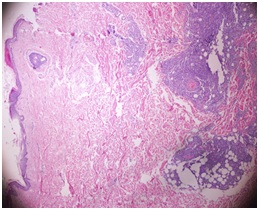

A Rare Follicular Lymphoma Case: Relapsed with Skin Involvement

Ugur MC, et al.